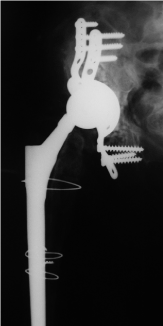

ROM was limited with extension / flexion 0/0/90°, abduction/adduction 10/0/10°, external rotation / internal rotation 10/0/10°. Scar was normal. There were no radiolucent lines concerning the stem. Two stage revision surgery due to septic loosening was performed elsewhere. In January reimplantation of the right hip was performed reconstructing of the acetabulum with a reinforcement device and a Wagner revision stem and 3 cerclage wires elsewhere. 3 weeks later rerevision was performed due to recurrent dislocation using a longer head.  Another dislocation occurred 2 months later with shortening of the right leg which was external rotated (Figure 3). Closed reduction was performed. 3 months later x-ray control was performed to evaluate the bony transplants (Figure 4). 2 years later in 2010 the patient presented herself again at our institution with no pain concerning her right hip but inability to walk; since several months she was using a wheel chair there was no history of trauma. The right leg seemed to be shortened and external rotated. ROM was painfully limited.

Figure 3.  X-ray of the right hip (ap view) shows a dislocated wagner revision stem with 3 cerclage wires and reconstruction of the acetabulum with massive bone transplants.